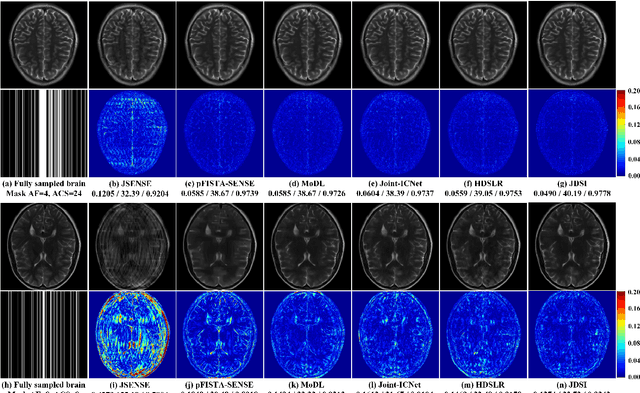

Abstract:Recent deep learning is superior in providing high-quality images and ultra-fast reconstructions in accelerated magnetic resonance imaging (MRI). Faithful coil sensitivity estimation is vital for MRI reconstruction. However, most deep learning methods still rely on pre-estimated sensitivity maps and ignore their inaccuracy, resulting in the significant quality degradation of reconstructed images. In this work, we propose a Joint Deep Sensitivity estimation and Image reconstruction network, called JDSI. During the image artifacts removal, it gradually provides more faithful sensitivity maps, leading to greatly improved image reconstructions. To understand the behavior of the network, the mutual promotion of sensitivity estimation and image reconstruction is revealed through the visualization of network intermediate results. Results on in vivo datasets and radiologist reader study demonstrate that, the proposed JDSI achieves the state-of-the-art performance visually and quantitatively, especially when the accelerated factor is high. Additionally, JDSI owns nice robustness to abnormal subjects and different number of autocalibration signals.